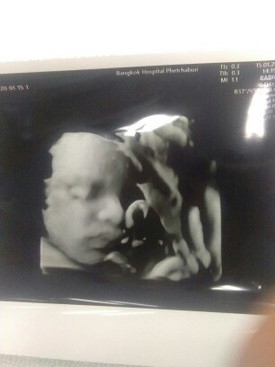

หล่อ ละมุนมากครับ บ้านนี้เห็นหน้าล่าสุดตอน 24 สัปดาห์ หลังจากนั้นก็หลบหน้ามาตลอด จนตอนนี้ 36+2 แล้ว คาดว่าจะได้ชมความหล่ออีกทีตอนคลอดเลยละครับ

โห... จมูกโด่งมาก. เราอยากไปซาวแบบนี้บ้างอะ แต่ไม่รู้ว่าไปซาวที่ไหนและแพงไหม.

น่ารักน่าซังมากค่ะ จมูกสวยมากค่ะแม่ฟุ้งปรี๊ดเลยค่ะ